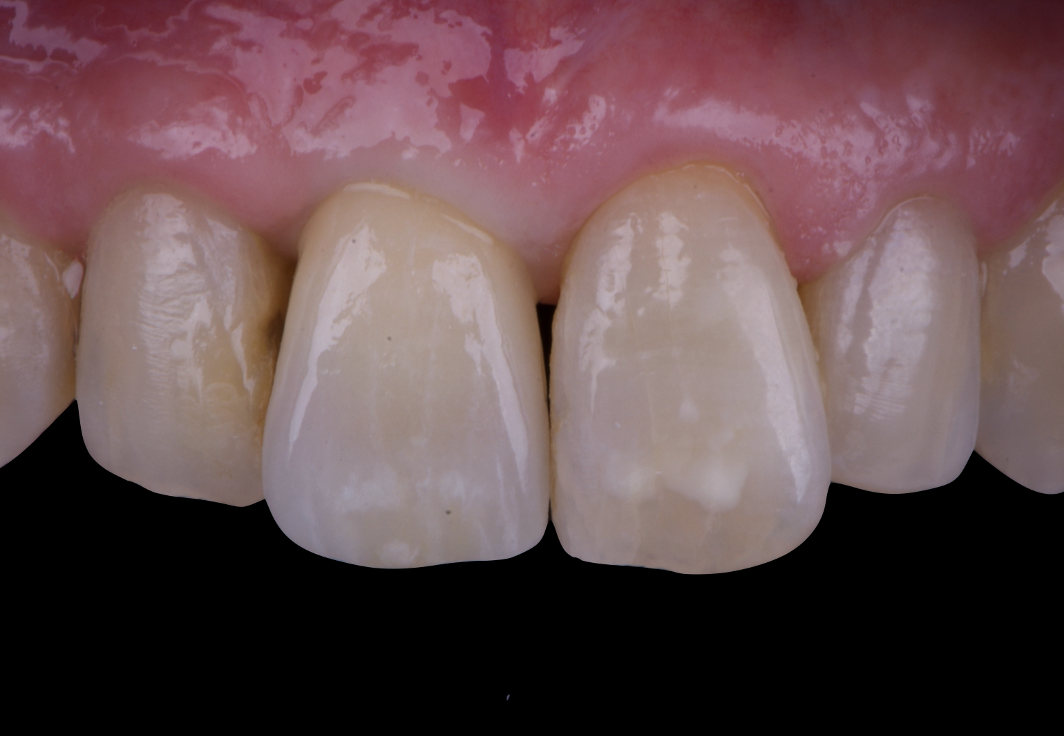

After an appropriate healing period, the definitive prosthesis was planned and delivered. A screw-retained zirconia crown was fabricated to ensure long-term durability, optimal esthetics, and retrievability. Zirconia was selected for its mechanical strength and excellent esthetic properties, blending seamlessly with the adjacent natural dentition in both form and color.

The final crown was designed to maintain the gingival architecture that had been shaped by the provisional. Special attention was paid to the emergence profile, contact points, and translucency to achieve harmony with the patient’s smile. The definitive restoration provided functional stability and esthetic integration, fulfilling the patient’s expectations for a fixed and natural solution.